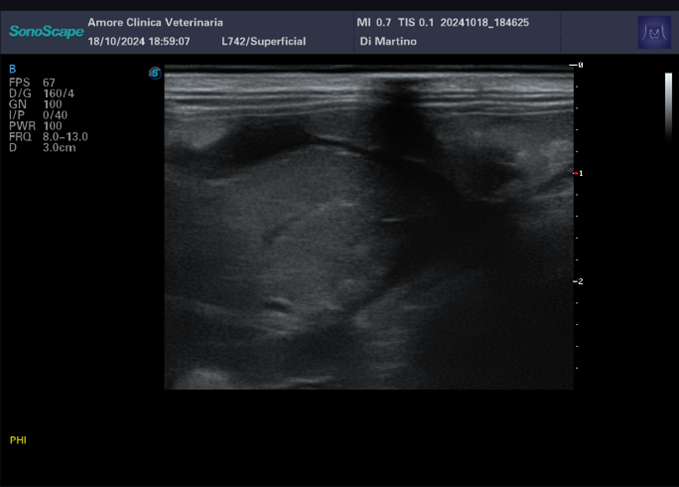

l’esame ecografico addominale rileva un dislocamento dell’apice del lobo epatico destro con presenza di una discreta falda di versamento ipoecogeno particolato.

Effettuata la centesi, il versamento risulta essere di tipo emorragico.